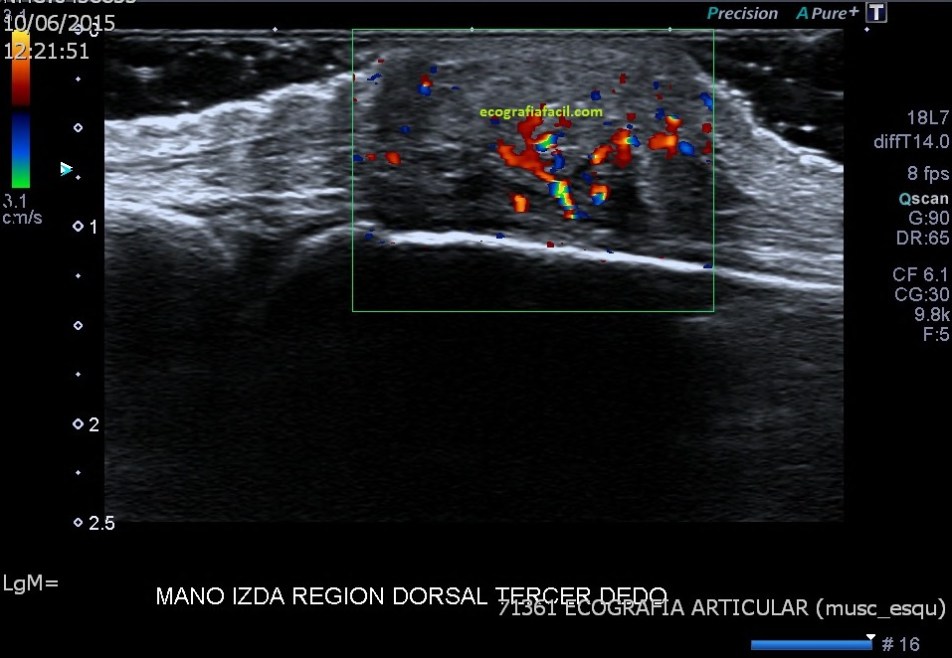

Se explora ecográficamente con sonda de alta resolución la región dorsal del tercer dedo de la mano izquierda, a la altura de la articulación metacarpofalángica.

Coincidiendo con el área palpable se identifica una lesión sólida de 13,8 x 9,6 x 17,8 mm, de aspecto heterogéneo, predominantemente hipoecogénica, aunque con áreas más hiperecogénicas en su interior, que predominantemente se encuentra superficial con respecto al tendón extensor del tercer dedo y con discreta vascularización periférica en el estudio Doppler color.

Es importante que la presión sea la justa, si observas la imagen 1 puedes ver como los vasos no está comprimidos.